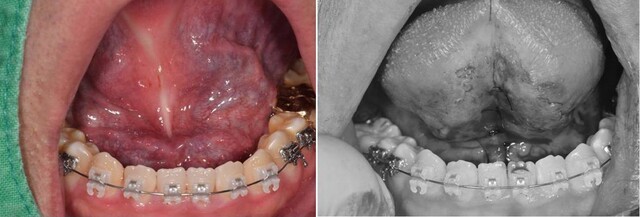

설소대 수술은 입안 아래쪽에 위치한 '설소대(혀밑띠)'가 비정상적으로 짧거나 두꺼워 혀의 움직임을 제한할 때 시행하는 시술입니다. 이 상태를 '설소대단축증'이라 하며, 어린 시기에는 발음 장애, 수유 곤란, 성장 후에는 음식 섭취나 구강 위생, 구강 구조의 발달에도 영향을 줄 수 있습니다.

수술은 국소 마취하에 짧은 시간 내에 진행되며, 설소대를 절개해 혀의 움직임을 보다 자유롭게 만들어 줍니다. 하지만 수술만으로 모든 치료가 끝나는 것은 아닙니다. 오히려 그 이후의 '재활 과정'이 혀의 정상적인 기능 회복에 핵심적인 역할을 합니다. 특히 발음, 삼킴, 구강 위생 등 일상생활의 다양한 기능에 혀가 깊이 관여하기 때문에, 수술 후 혀의 움직임을 올바르게 회복시키는 운동은 반드시 필요합니다.

짧은 설소대는 혀를 비정상적인 위치에 고정시키며, 그로 인해 움직임 자체가 제한된 상태로 굳어집니다. 수술을 통해 물리적 제약은 해소되었지만, 오랫동안 잘못된 위치와 움직임에 익숙해진 혀 근육은 여전히 그 패턴을 기억하고 있습니다. 이러한 상태에서는 단순한 수술만으로는 충분하지 않으며, 근육과 신경계가 새로운 움직임을 학습할 수 있도록 '훈련'이 반드시 병행되어야 합니다.